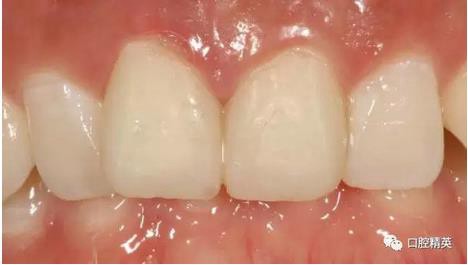

修復(fù)體展示

修復(fù)體戴入

口內(nèi)正側(cè)位及切端特寫

有一點(diǎn)不足之處在于齦緣的高低不完全一致,補(bǔ)救辦法同上——激光輕掃